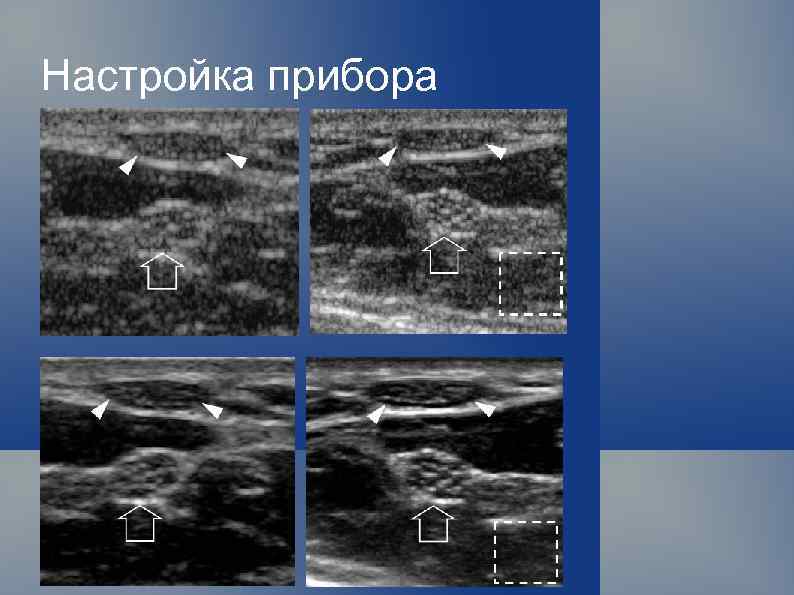

Настройка прибора